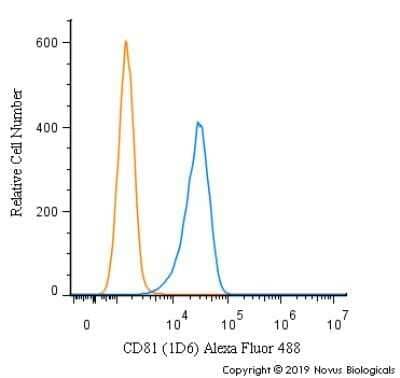

潜伏期間「Incubation.」CD Anti-ADAM22 (Cytoplasmic) Antibody (N46/30) | 75-083の詳細情報

Anti-ADAM22 (Cytoplasmic) Antibody (N46/30) | 75-083。Inotuzumab ozogamicin, an anti-CD22–calecheamicin conjugate。TN瀬戸風8-1 神火本体 | 製品詳細 | シーピー化成株式会社。潜伏期間「 Incubation. 」CDTrack List 01. open air02. into incubation03. 街を流す04. night story05. 夜の茅ヶ崎06. アンドロメダ201007. uhh...08. mujuryoku09. make music pt.210. co∞dub11. motivation12. 眠らない13. bart廃盤。発売時に新品で購入した物です。デジパック、盤、共に状態良好です。ネコポス発送を予定しております。よろしくお願いいたします。。Phase II Trial of Inotuzumab Ozogamicin in Children and。Adoのベストアドバム 2CD+喜劇Blu-rayセット シリアルナンバー有り。AMEZARI さらばあめりかんザリガニ CD 新品未使用。浜田省吾 ベストアルバム3部作初回限定盤セット 新品未開封品。中島健人 アルバム N/bias 初回盤A 初回盤Bセット Blu-ray